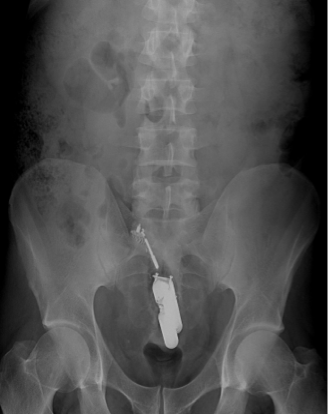

Radiopaque vs. Radiolucent

•Radiopaque

–Difficult to penetrate

–Bone, metal

•Radiolucent

–Easy to penetrate

–Air, soft tissue